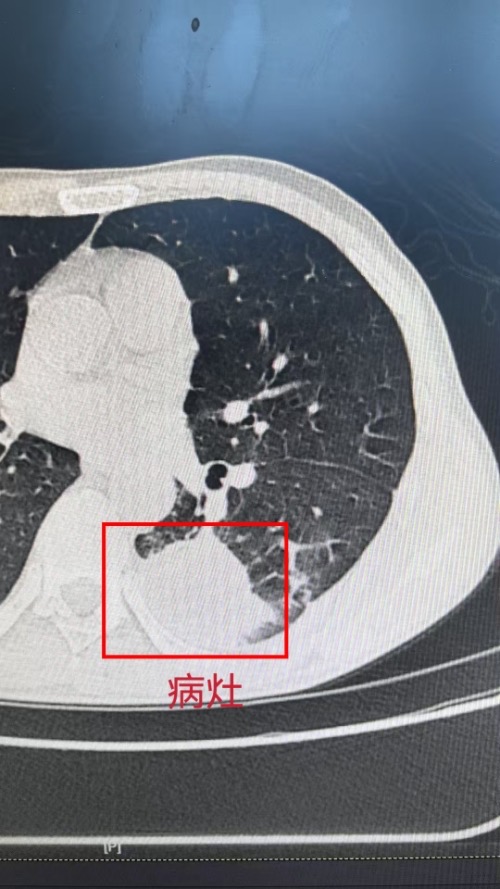

在手术过程中,团队面临着诸多的挑战。由于患者本身患有白血病,肺部病灶达43*36mm,并且病灶靠近肺门血管,胸腔粘连严重,手术操作难度大,风险高,稍有不慎,患者可能出现难以控制的出血及呼吸衰竭等并发症。凭借着丰富的临床经验和精湛的医疗技术,整个手术过程顺利,出血量少,术后患者生命体征平稳。